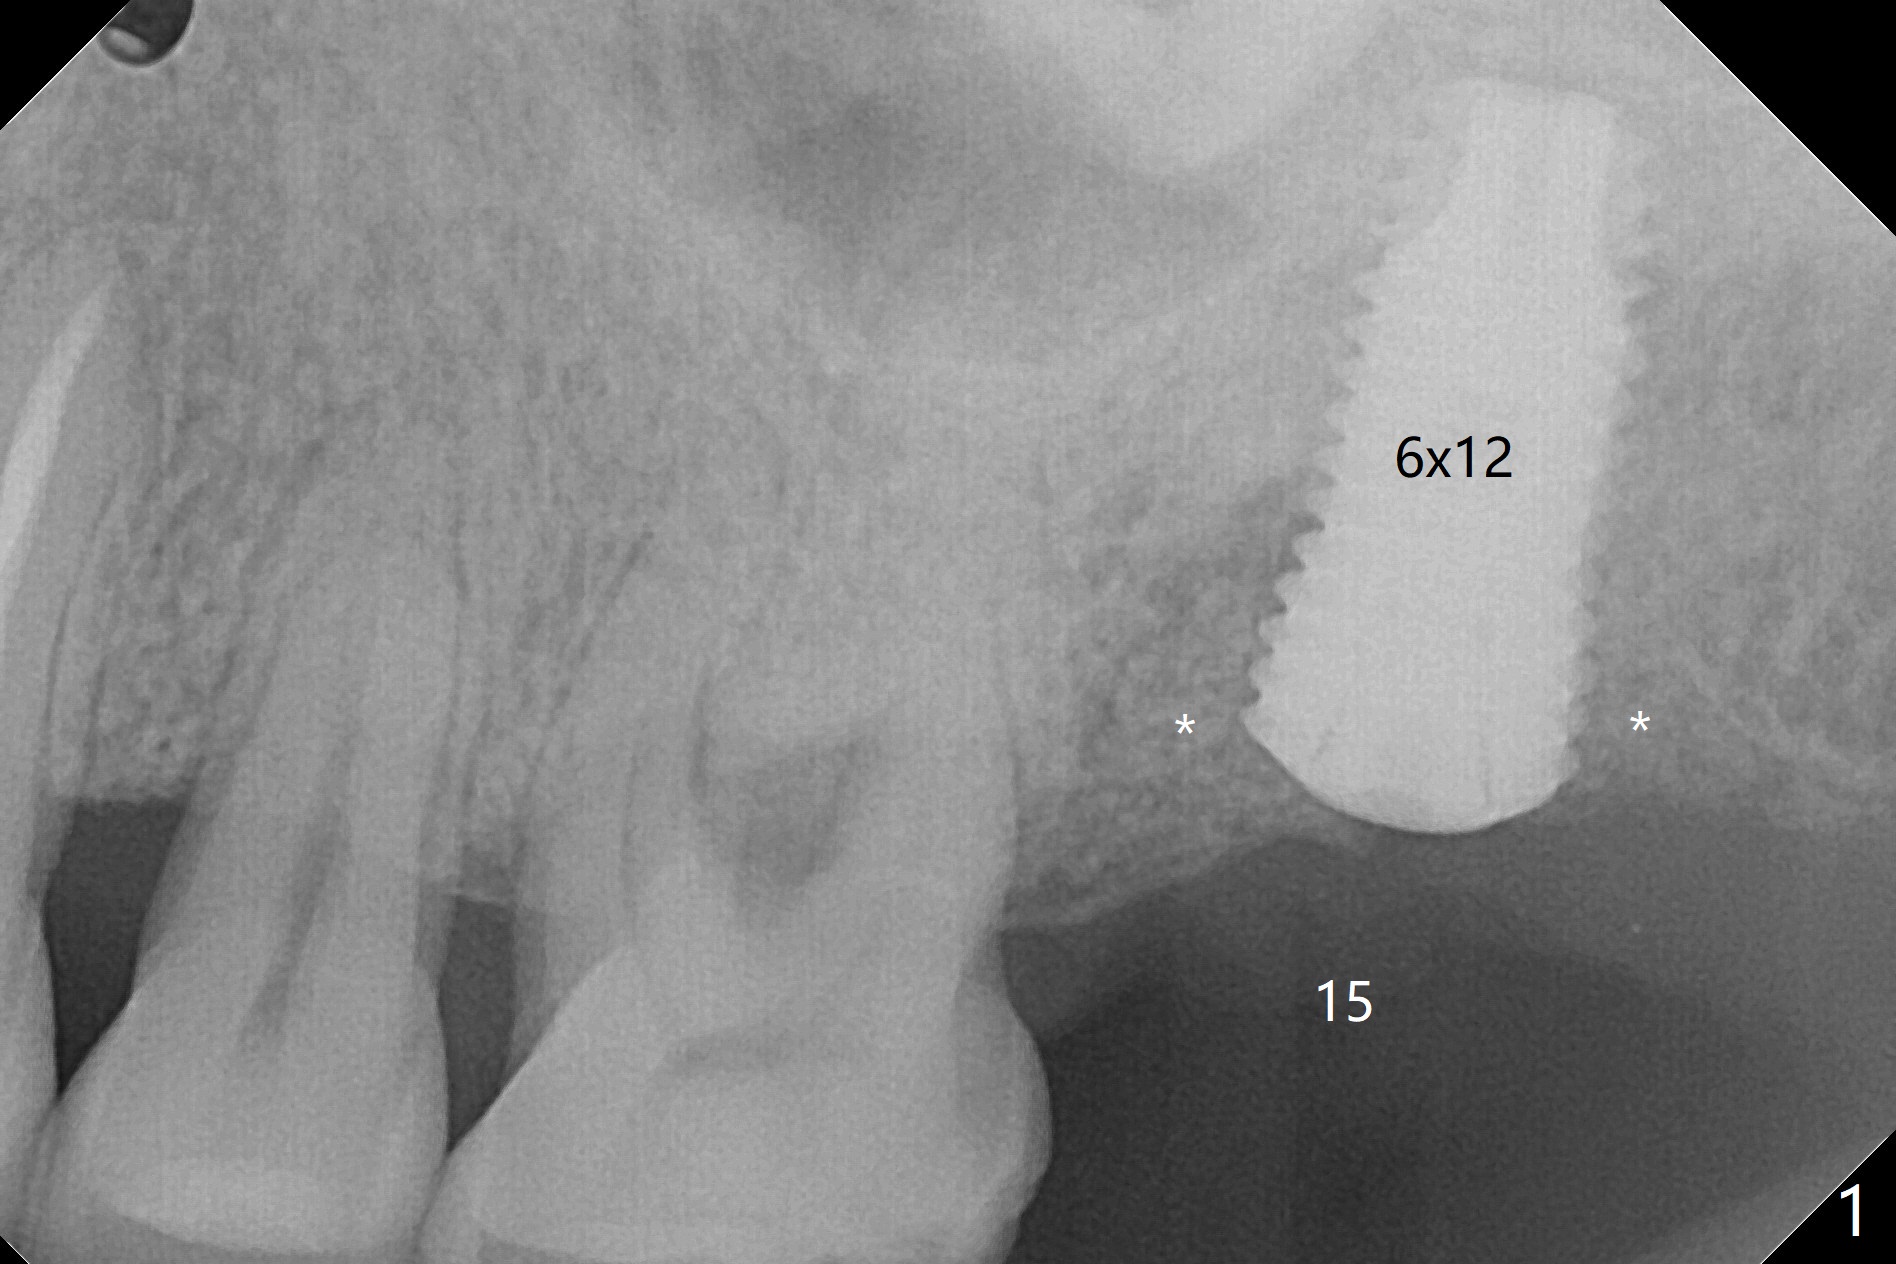

59岁男一年前因15号牙植牙周围炎去除牙冠和基台,植骨(图一:*(其实是第二次为周围炎植骨)),缝合。之后局部疼痛没有完全消失,准备再次手术(切开),如果螺纹暴露少,再次植骨。否则拔除植体(图二:黑色,手术探查的确不能挽救植体),之后有两个选择植骨(图三:灰色)或者即刻再次种植。由于原来植体比较粗(骨水平;6x12毫米),利用6(内径)/7(外径)毫米trephine drill和牙挺除去植体,留下相当大缺损(图二),植骨后(图三),位于缺损中间的骨粉(图四:棕色)可能因血供(红箭头)不足而愈合不佳。因此即刻重新种植显得有优势(图五(软组织水平植体,螺纹在自身骨(native bone)下)),让身体不必太辛苦(成骨)。放置5x5毫米基台目的是为树脂敷料提供固定点,以防PRF膜和缝线不能挽留粘性骨粉(*)。术后一个月撤除树脂敷料,伤口愈合正常(图六)。准备一个月后,制作临时牙冠。术后4个月取出5x5毫米基台,准备放置6x5毫米基台(图七),下面软组织水平植体没有疼痛或者松动,螺纹被骨粉或者再生骨质覆盖(^)。